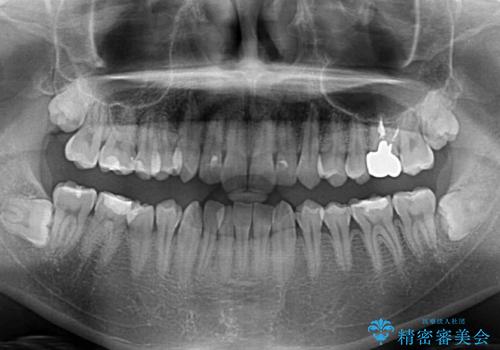

上下ともに叢生が認められたため、親知らずすべてを抜歯し、歯列全体を後方へ移動させることで歯列を整えることとしました。

上顎奥歯の銀歯も気になっていたので、矯正治療の途中でセラミッククラウンへ変更し、その後歯列を仕上げていくこととしました。

ディープバイトもデコボコも改善され、気になっていた銀歯もセラミックとなり、患者様には大変満足していただきました。